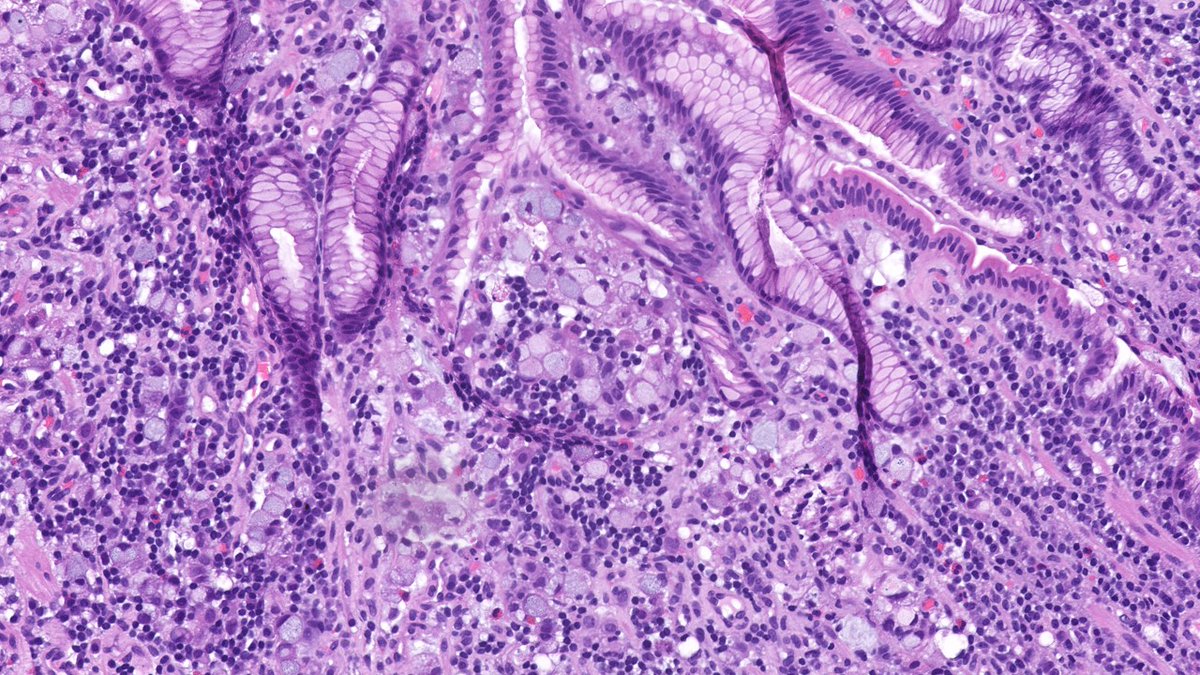

Diffuse type gastric adenocarcinoma with signet ring cells

Gastric biopsy from a 53-year-old male. What is your diagnosis?